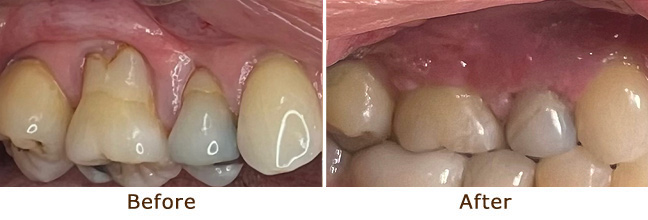

Gum Lifting and Gum Grafting

Gum Graft

Gum Graft